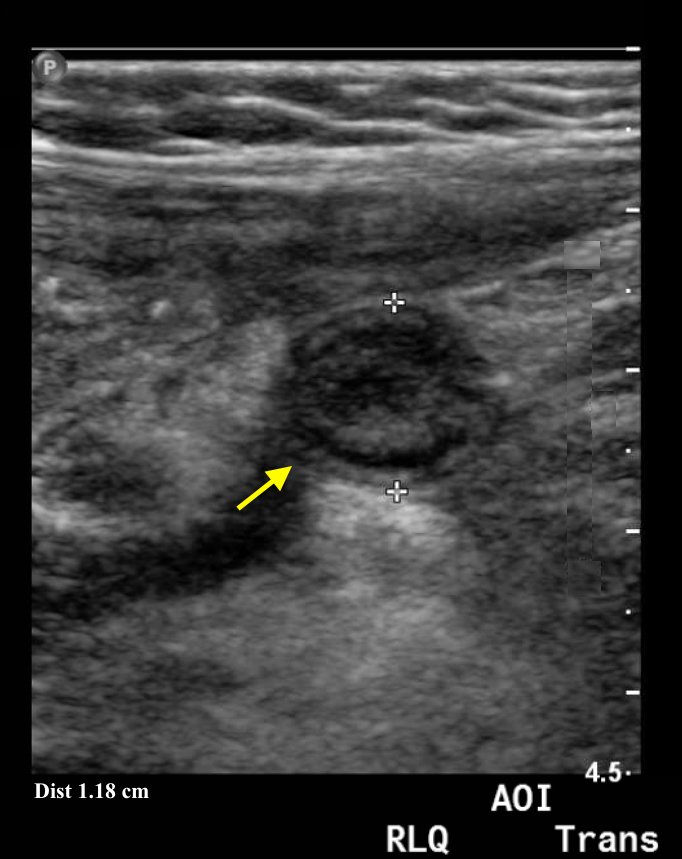

In the long axis video, the appendix appears as an enlarged, non-compressible, blind-ending tubular structure (white arrow) with distinct appendiceal wall layers and lack of peristalsis. In the short axis video, the appendix appears as a target sign (yellow arrow) between the abdominal and psoas muscles. The maximal outer diameter (MOD) measures 11.8mm and the appendix wall measures 0.17mm. There is trace adjacent free fluid and echogenic periappendiceal fat. Transverse axis video and image (red arrow) demonstrate that the appendix is not compressible. These findings are consistent with acute appendicitis.